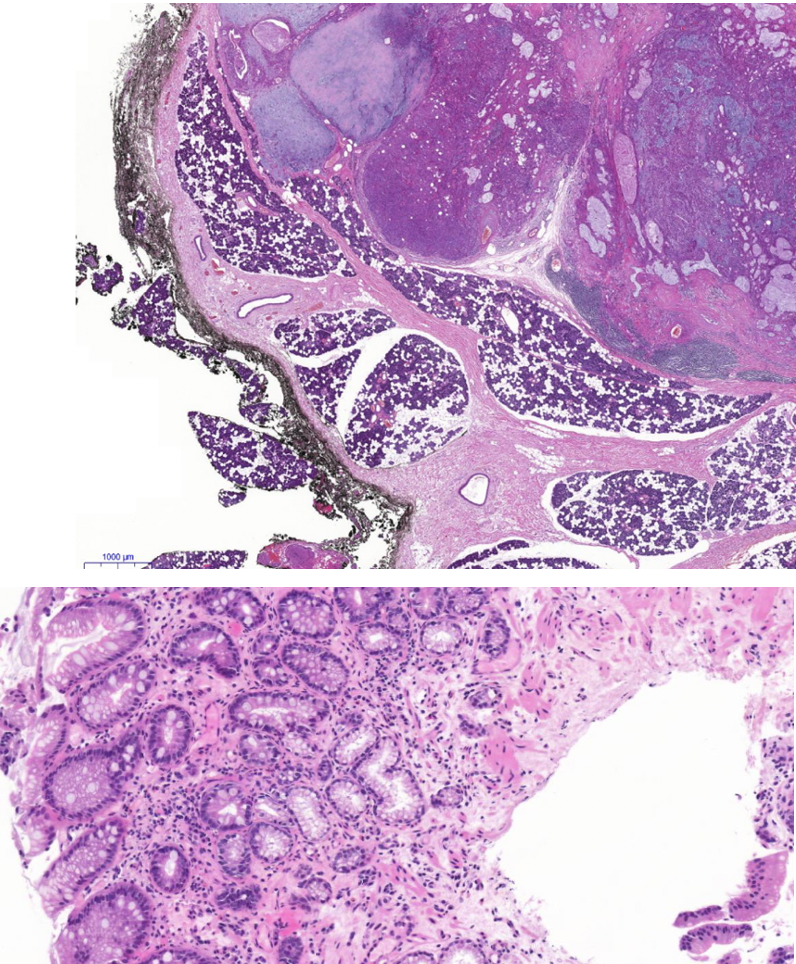

Diagnose?

Barettmetaplasie (dunkelviolett = mit Dysplasie)

Durch Reflux -> Metaplasie (nicht maligne) der Epithelien, intestinalisiertes Epithel/ Becherzellen, Biopsate mit Plattenepithel und Zylinderepithel (nur dann weiß man es ist Übergangsbereich)

Barrett-Zelle = Becherzelle